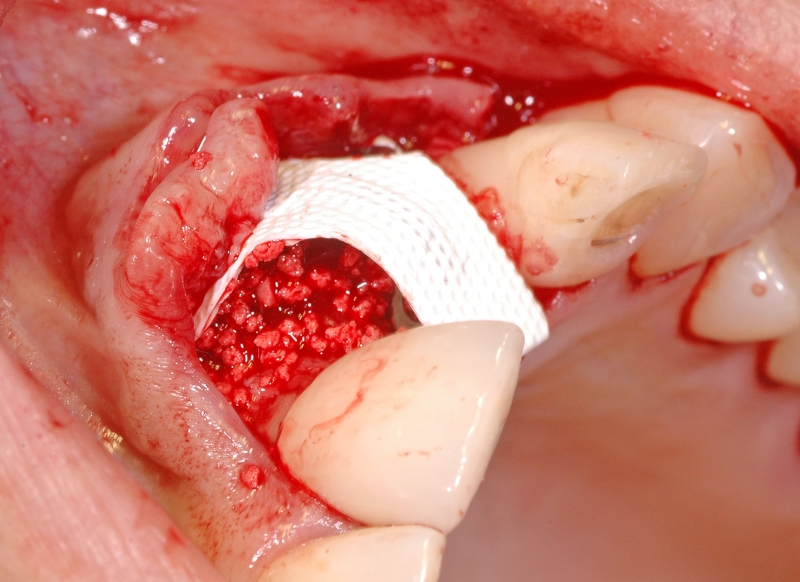

6/18 - Augmentation with maxresorb® and covering with a non-resorbable PTFE membraneGBR together with soft tissue augmentation with mucoderm® and maxresorb® - Dr. S. Scherg